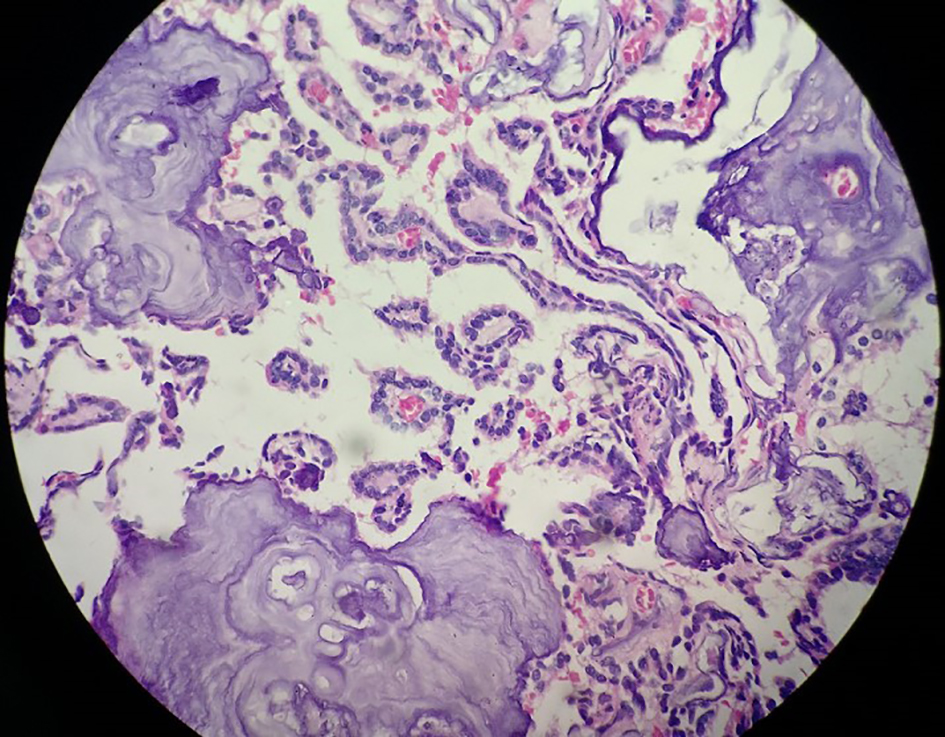

Complete removal of the tumor mass was done after securing the vascular supply. There was no element of obstruction. The frozen section and histopathological findings of the excised tumor mass (Microsections showed fibrovascular fronds lined by cuboidal to low columnar cells with extreme area of calcification and focal areas of chondroid and osseous metaplasia in the stroma. No mitosis or necrosis was seen.) were diagnostic of CPP (WHO grade I) (Fig. 4). The immunohistochemistry study showed positivity for cytokeratin (CK7) (Fig. 5) and S-100 (Fig. 6). The patient had an uneventful postoperative period. During the postoperative follow-up after 4 months, the patient was completely symptom free and her visual acuity had improved considerably.

![]() Click for large image | Figure 4. Histopathological image showing fibrovascular fronds lined by cuboidal to low columnar cells with extreme area of calcification and focal areas of chondroid and osseous metaplasia in the stroma. |

CPPs belong to this group of lesions, and are histologically identified by a complex array of branching fibrovascular fronds covered by a monolayer of uniform cuboidal or low columnar epithelial cells. Nuclear atypia minimal and little mitotic activity (less than 2/10 high power field (HPF)) are seen. Stroma is infiltrated with foamy macrophages and may be pigmented by melanin. Areas of calcification, metaplastic bone or cartilage formation may be present. Epithelium may show oncocytic change, and may assume foci of ependymal differentiation producing GFAP-immunoreactive tapering cytoplasmic processes towards their fibrovascular cores. Exceptional cases exhibit a glandular growth pattern designated as acinar or tubular choroid plexus adenoma, confused with metastatic adenocarcinoma. Most peculiar is the CPP exhibiting overt neuronal differentiation, signaled by micronodular collection of synaptophysin rich matrix.